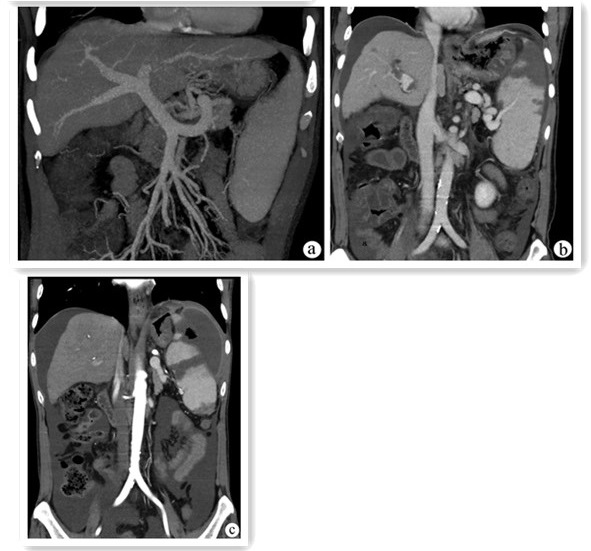

三维可视化消融辅助系统在肝细胞癌射频消融术中的应用价值

赫嵘, 贾哲, 蒋力, 张珂

摘要:

目的  探讨三维可视化消融辅助系统在肝细胞癌射频消融术中应用的意义。  方法  选取2017年7月—2020年12月于首都医科大学附属北京地坛医院因肝细胞癌行射频消融治疗的患者71例,其中三维组(n=34)术前应用三维可视化消融辅助系统进行射频方案规划,二维组(n=37)术前应用二维影像进行射频方案规划。比较两组患者的一次穿刺成功率、肿瘤完全消融率、无瘤生存期等。计数资料两组间比较选择Fisher精确检验、连续校正的χ2检验或Pearson χ2检验;符合正态分布的计量资料两组间比较采用t检验,非正态分布的计量资料两组间比较采用Mann-Whitney U检验;Kaplan-Meier法绘制生存曲线,Log-rank(Mantel-Cox)检验比较肿瘤复发和生存情况,通过Cox比例风险回归模型分析无瘤生存期的影响因素。  结果  三维组一次性穿刺成功率(94.12%)高于二维组(75.68%)(Pearson χ2=4.183,P=0.041),三维组术中穿刺耗时中位时间(5 min)低于二维组(7 min)(Z=-2.407,P=0.013)。三维组和二维组的消融完全率分别为97.06%和91.89%,两组差异无统计学意义(连续矫正χ2=0.183,P=0.669)。在1、2、4年累积无瘤生存率比较中,三维组分别为90.8%、78.8%和72.8%,二维组分别为61.5%、55.9%和44.7%, 两组差异有统计学意义(χ2=5.073,P=0.024)。多因素Cox回归分析结果显示,术前规划方式、消融是否完全、术后1个月AFP水平为肝细胞癌患者射频消融术后无瘤生存期的独立影响因素(P值均<0.05)。  结论  通过三维可视化消融辅助系统进行肝细胞癌射频消融规划,可以保证射频消融的疗效,降低肝细胞癌复发率,延长患者的无瘤生存期。